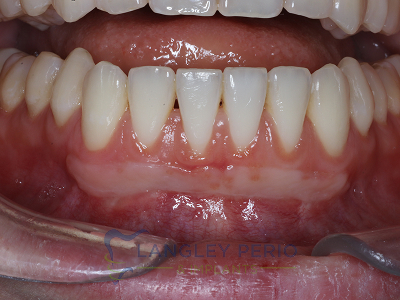

Case 1

Connective tissue grafting was performed to correct gingival clefting caused by over-aggressive toothbrushing